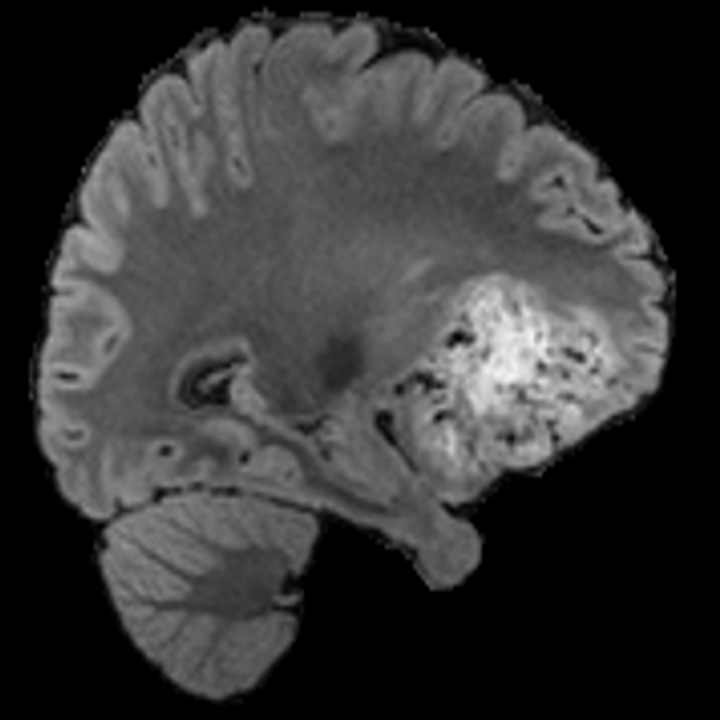

Tumour Information Preservation. For the brain tumor segmentation, we use a Swin UNETR model[27, 70], trained with random rotation, and intensity as data augmentation. In Figure 5, we highlight the tumor profiles of the generated MRIs compared to the ground truth tumour profile. In the test set with human ground-truth annotations (), the real MRI Dice score is 85.15 while the generated MRIs from a single slice have a dice score of 83.09. This shows how the generated MRIs indeed preserve the tumor information and can act as an affordable and informative pseudo-MRI, before conducting an actual costly MRI examination in hospitals.

B.4 Tumour Information Preservation

On the test set with human ground-truth annotations (), the brain volumes generated from single slice input preserve the volume of the different tumour components (paired t-test, for all 3 classes) (see Table 3). The real MRI Dice scores are put for reference to our generated MRIs. X-Diffusion outperforms baselines TPDM [36] and ScoreMRI [18] in tumour preservation (see Table 3 and Figure 12). We ran experiments comparing the tumour segmentation Dice Score varying X-Diffusion configurations. The multi-slice input X-Diffusion achieves a marginally better Dice Score than the single-slice input model (83.47 83.09). We also ran experiments with slice input used for volume reconstruction intersecting or not with tumour. We observe on average a drop of 6% Dice Score (see Table 3). Further away from the tumour the input slice for volume reconstruction is selected, and we observe a linear decrease in tumour segmentation Dice Score with the lowest value of 77.21 Dice Score (see Figure 15).

This shows how the generated MRIs indeed preserve the tumour information and can act as an affordable and informative pseudo-MRI, before conducting an actual costly MRI examination in hospitals. Given that our model has been trained on brain scans all with tumours, we expect to see hallucinations of tumours in healthy scans. We report two cases of failure of our model in Figure 16. Hallucinations of tumours on healthy samples represent 2% of the test set.